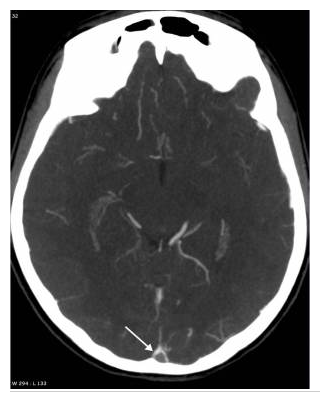

Thrombose du sinus sagittal supérieur en scanner.

Coupe axiale après injection de produit de contraste iodé : signe du delta au niveau du sinus sagittal supérieur thrombosé (flèche) ; le thrombus hypodense est moulé par les parois du sinus qui prennent le contraste.